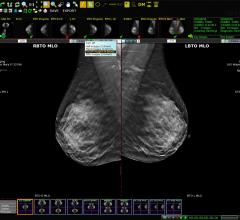

Information technology (IT) is among the least sexy areas to cover in medical technology advances, and is often difficult to find really interesting news as I sift through more than 1,300 vendors at the massive annual Health Information and Management Systems Society (HIMSS) conference. However, at this year’s conference I found two exciting new technologies that I feel have the potential to become paradigm shifts in medicine. The first is the integration of artificial intelligence into medical imaging IT systems. The second, and coolest tech at HIMSS, was the use of augmented reality 3-D imaging visors to create a heads-up display of 3-D imaging anatomical reconstructions, or complete computed tomography (CT) or magnetic resonance imaging (MRI) datasets surgeons can use in the operating room (OR).

After attending HIMSS, I actually feel energized about the prospects artificial intelligence (AI) may offer medicine. But, unlike the science fiction image that snaps into most people’s minds when you talk about AI, it will not be a cool, interactive, highly intelligent robot that will replace doctors. In fact, most users will not even be aware AI is assisting them in the backend of their electronic medical record (EMR) systems. AI is a topic that has been discussed for a few years now at all the medical conferences I attend, but I saw some of my first concrete examples of how AI (also called deep learning or machine learning) will help clinicians to significantly reduce time and workflow efficiency. AI will accomplish this by working in the background as an overlay software system that sits on top of the PACS, specialty reporting systems and medical image archives at a hospital.

The AI algorithms are taught through machine learning to recognize complex patterns and relations of specific types of data that are relevant to the image or disease states being reviewed. In one example I saw from Agfa’s new integration of IBM Watson’s AI, the system was smart enough to look at a digital X-ray image and realize the patient had lung cancer and evidence of prior lung and heart surgeries. It automatically searched for specific records for the patient from oncology treatments, cardiology, prior chest exams from various modalities, recent lab results and relevant patient information on their history of smoking.

Philips Healthcare showed its Illumeo adaptive intelligence software, which uses AI to speed workflow. The example demonstrated was for oncology, where a computed tomography (CT) exam showed several tumors. The user can hover and click on a specific piece of anatomy on a specific slice and orientation. The system then automatically pulls in prior CT scans of the game region and presents the images from each exam in the same slice and orientation as the current image. If the AI determines it is a tumor, the system also runs auto quantification of the tumor sizes from all the priors and presents them in a side-by-side comparison. The goal of the software is to greatly speed up workflow and assist doctors in their tasks.

AI is also making its appearance in business and clinical analytical software, as well as imaging modality software, where it can automatically identify all the organs and anatomy, orientate the images into the standard reading reviews and perform auto quantification. This is already available on some systems, including echocardiography for automated ejection fractions and wall motion assessments.